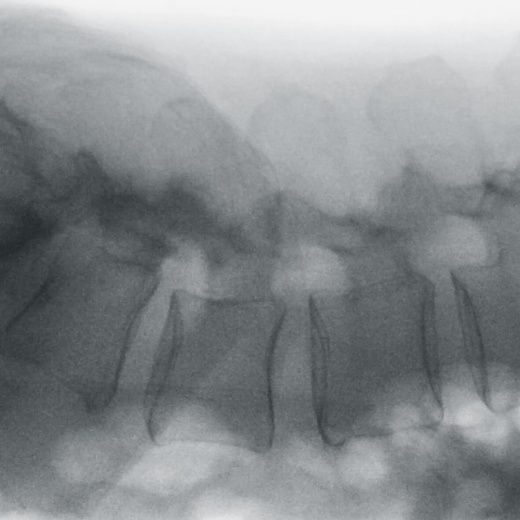

Полное отсутствие искажений снимков в сочетании с высоким динамическим диапазоном широко востребованы как при сложных операциях в нейрохирургии, сосудистой хирургии, инвазивной радиологии, так и в гибридных областях применения, а также в ортопедии, травматологии. В сосудистой хирургии особенно важны высокий динамический диапазон и пространственное разрешение, обеспечивающие детальную визуализацию даже мельчайших сосудов. Специализированное программное обеспечение SmartVascular позволяет проводить настройку системы для васкулярных операций и сосудистой хирургии.

Точная визуализация анатомических деталей, мягких тканей и костных структур обеспечивается за счет светочувствительной матрицы 3kх3k пикселей с высоким динамическим диапазоном.

Винты, пластины, импланты и хирургические инструменты автоматически распознаются при попадании в видимое поле аппарата. В этом случае происходит корректировка мощности дозы облучения для улучшения качества снимка.